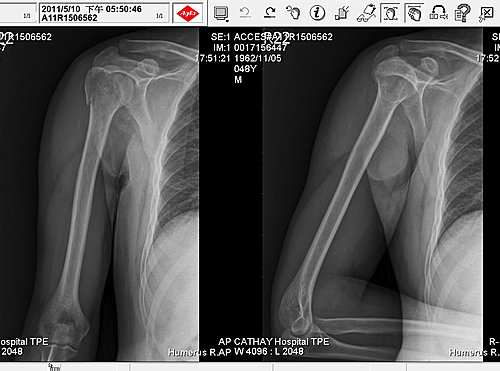

2011.05.10 拍攝的X光圖